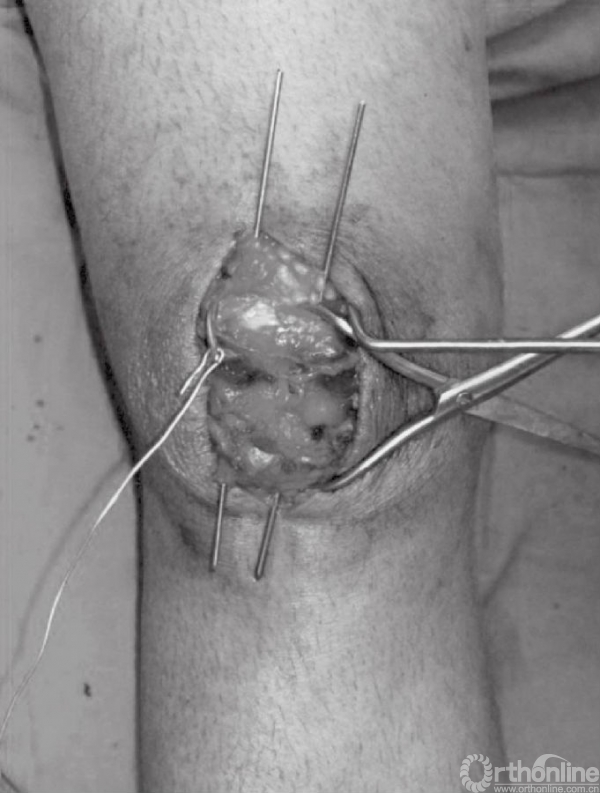

深层显露切口与皮肤切口方向一致。锐性分离深层筋膜,并牵开皮肤组织,进一步切开髌骨囊并清除血肿后骨折端即可显露(图4A和B)。此时,可见髌骨骨折以及撕裂的韧带。以生理盐水清洗血肿以及血凝块(图5)。撕裂的支持带可先辨识后,再进行修复。

图4 A和B切开髌骨关节囊,清除血肿后显露骨折块。图示髌骨横断型骨折,可见韧带撕裂